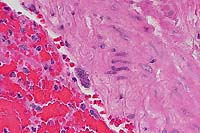

- Case 5-1. Immunohistochemical stain for BVD virus

structural & non-structural proteins

- Note positive staining of blood vessel tunica media.

- Immunohistochemistry: Immunohistochemistry was performed

on snap-frozen sections of skin, thyroid gland, tongue and abomasum

collected at necropsy. Immunohistochemistry of the heart was

performed on paraffin-embedded tissue. Four monoclonal antibodies

against BVD-virus structural and non-structural proteins were

applied using the LSAB-method. All organs examined were positively

labeled. A positive control from a reference calf was run with

each batch of monoclonal antibodies. A negative control with

PBS (pH 8) was made with each slide.

- Contributor's Diagnosis and Comments: Heart: Moderate

subacute perivasculitis and vasculitis. Mild multifocal subacute

myocarditis. Lung: Severe chronic bronchointerstitial pneumonia

- The heart is submitted for Wednesday Slide Conference. The

perivascular region and the vessel walls are infiltrated with

mononuclear inflammatory cells. The endothelial cells are activated,

and in some regions there is a hyaline degeneration of the vessel

wall. This vasculitis was seen in the brain, intestine (vessels

of the submucosa), and the heart.

20x

obj.

AFIP Diagnosis: Heart, myocardium: Vasculitis and perivasculitis,

lymphohistiocytic and plasmacytic, multifocal, moderate, with

vascular fibrinoid necrosis, mild interstitial edema, and myocardial

necrosis, Brown Swiss, bovine.